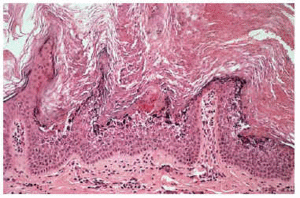

Niña de 6 años de edad, sin antecedentes persona-les ni familiares de interés, que consultó por la presencia de unas placas de superficie rugosa y áspera distribuidas en bandas por todo su hemicuerpo izquierdo desde el nacimiento. A la exploración encontramos placas verrugosas hiperqueratósicas de color amarillento, distribuidas siguiendo las líneas de Blaschko, afectando las extremidades superior e inferior izquierdas, así como la hemicara izquierda, y especialmente el hemitronco izquierdo, con un límite claro en la línea media (fig. 1). El resto de la exploración física fue normal. Realizamos una biopsia del abdomen, que demostró una hiperqueratosis compacta, así como una degeneración vacuolar y granular de los estratos espinoso y granuloso de la epidermis, es decir, un patrón histológico de hiperqueratosis epidermolítica (fig. 2). La analítica básica, incluyendo hemograma y bioquímica, no mostró alteraciones.

Fig. 2.--Hiperqueratosis epidermolítica.

El término hiperqueratosis epidermolítica define un determinado patrón histológico (hiperqueratosis compacta con degeneración granular y vacuolar de las capas espinosa y granulosa de la epidermis) que puede aparecer en cuadros clínicos muy distintos: EICA, queratodermia palmoplantar, nevo epidérmico, acantoma epidermolítico e incluso como hallazgo incidental en la piel normal al biopsiar una gran variedad de procesos tumorales o inflamatorios5-7.